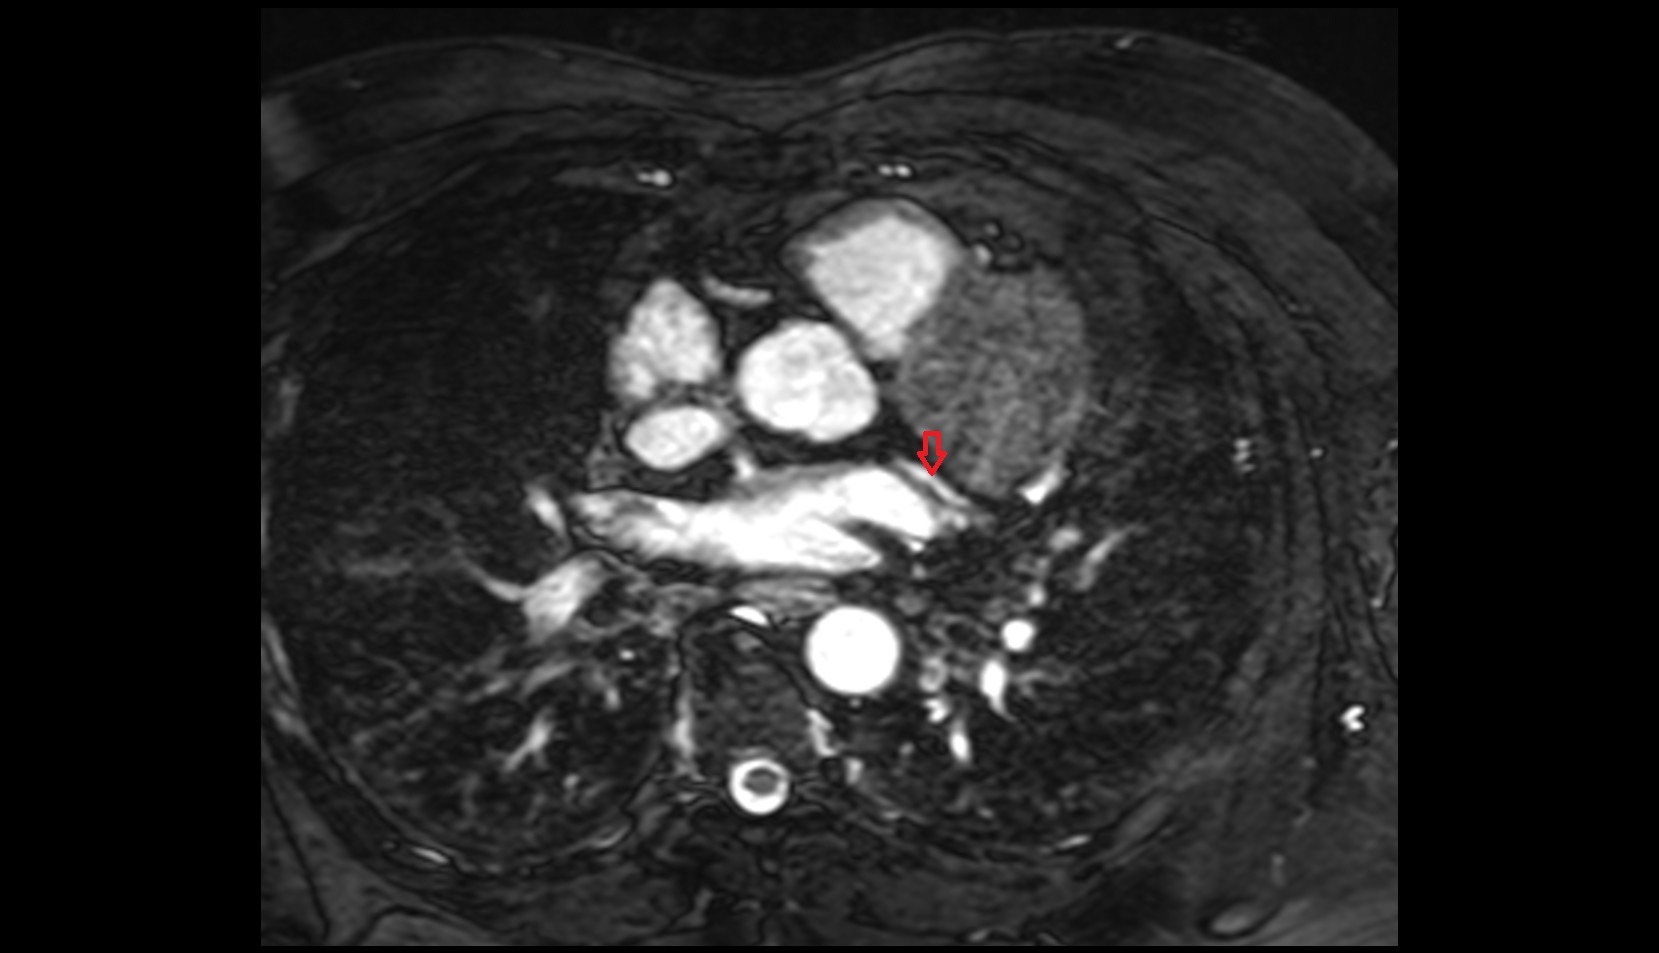

- Left anterior descending artery (LAD)

- Circumflex artery (LCx)

- Left main coronary artery (LMCA)

- Right coronary artery (RCA)